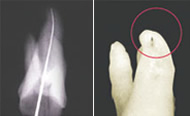

Raypex® – Apexlocator zur exakten Längenbestimmung eines Wurzelkanals

Die Basis jeder erfolgreichen Wurzelbehandlung ist die exakte Längenbestimmung des zu behandelnden Wurzelkanals.

• Endometrie als sicherste Methode zur Längenbestimmung anerkannt

• Aktuelle Stellungnahme der DGZMK: Elektrische Längenbestimmung ist genauer als Röntgen

• Die herkömmliche Röntgendiagnostik ist nur bedingt aussagefähig, da 2–D Abbildungen einer 3-D Kanal-Morphologie

Die unvollständige Information eines zweidimensionalen Röntgenbildes kann zum Misserfolg führen. Quelle: VDW